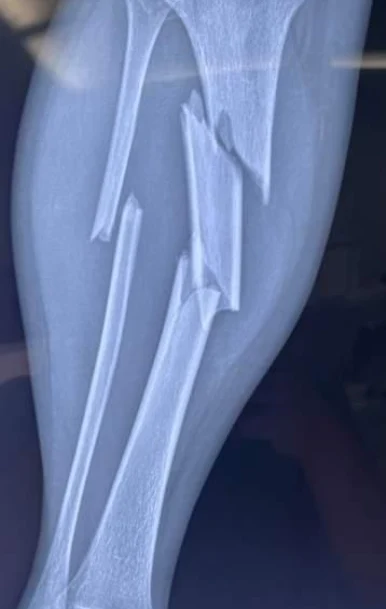

影像学检查是诊断胫骨骨折的金标准,首选的影像学检查手段是X线摄片。通过X线片,可以清楚地观察到骨折的形态、移位情况以及骨折线走向。在某些复杂病例中,可能需要进一步进行CT扫描或MRI检查,以更清楚地了解骨折的细节和周围软组织的损伤情况。

最后,根据骨折形态,胫骨骨折可分为不完全骨折和完全骨折;不完全骨折包括骨裂和青枝骨折,完全骨折则包括横断骨折、斜行骨折、螺旋形骨折和粉碎性骨折。此外,还有特殊类型骨折,如移位性和非移位性骨折、开放性和闭合性骨折等。